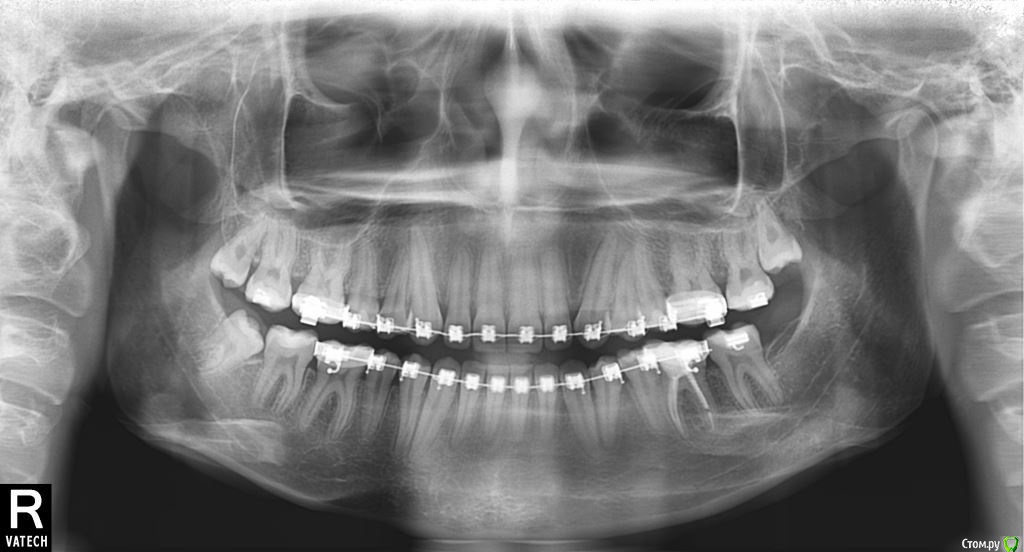

Айсылу Опубликовано 12 мая, 2015 Поделиться Опубликовано 12 мая, 2015 Здравствуйте. Помогите, пожалуйста, разобраться в сложной ситуации возникшей в процессе лечения. В августе 2013 года мне была установлена брекет-система. Изначально была проблема глубокий прикус. В результате выравнивания у меня сформировался дистальный прикус. После чего, мой лечащий врач, порекомендовала удалить две 4-ки на ВЧ. Это произошло примерно через год. Самое интересное, что удалить мне сказали один из тех зубов, который мы все это время выравнивали. По сей день я на это не решилась. Обращалась к еще 3-м специалистам. Один сказал удалять, двое категорически были против. Сказали, что в результате будет нарушена эстетика лица. Мне посоветовали сделать анализ ТРГ в независимом диагностическом центре. Хотела спросить у Вас, уважаемые специалисты данного форума, что вы можете сказать по результатам данного анализа? Живу я в маленьком городе. Особо обратится не к кому.А удалять зубы страшно. И если не трудно, расскажите, напишите, каким образом возможно исправить данный тип прикуса. Хожу в брекетах уже 1 год и 10 месяцев. Ссылка на комментарий

Айсылу Опубликовано 23 июля, 2015 Автор Поделиться Опубликовано 23 июля, 2015 Здравствуйте. Снова я с вопросом к Вам, уважаемые, ортодонты. Вот сделала такие снимки. Ортодонт из "Большого города" сказал, что суставные головки на месте и что выдвигать нижнюю челюсть нельзя. Расширять НЧ уже поздно, из-за возраста. Три варианта решения проблемы мне предложили.:1. Удалить 4-ки (предупредил, что удаление приведет к деформации черепа);2. Хирургическим путем (на этот метод я никогда не решусь);3. снять брекеты. Я записалась на снятие. Для успокоения души решила еще и Ваше мнение узнать... Единственное меня беспокоит тот момент, на сколько губителен этот мой новый дистальный прикус. И что хуже, глубокий прикус, который был до лечения, или же этот, который возник у меня процессе лечения.? Ссылка на комментарий